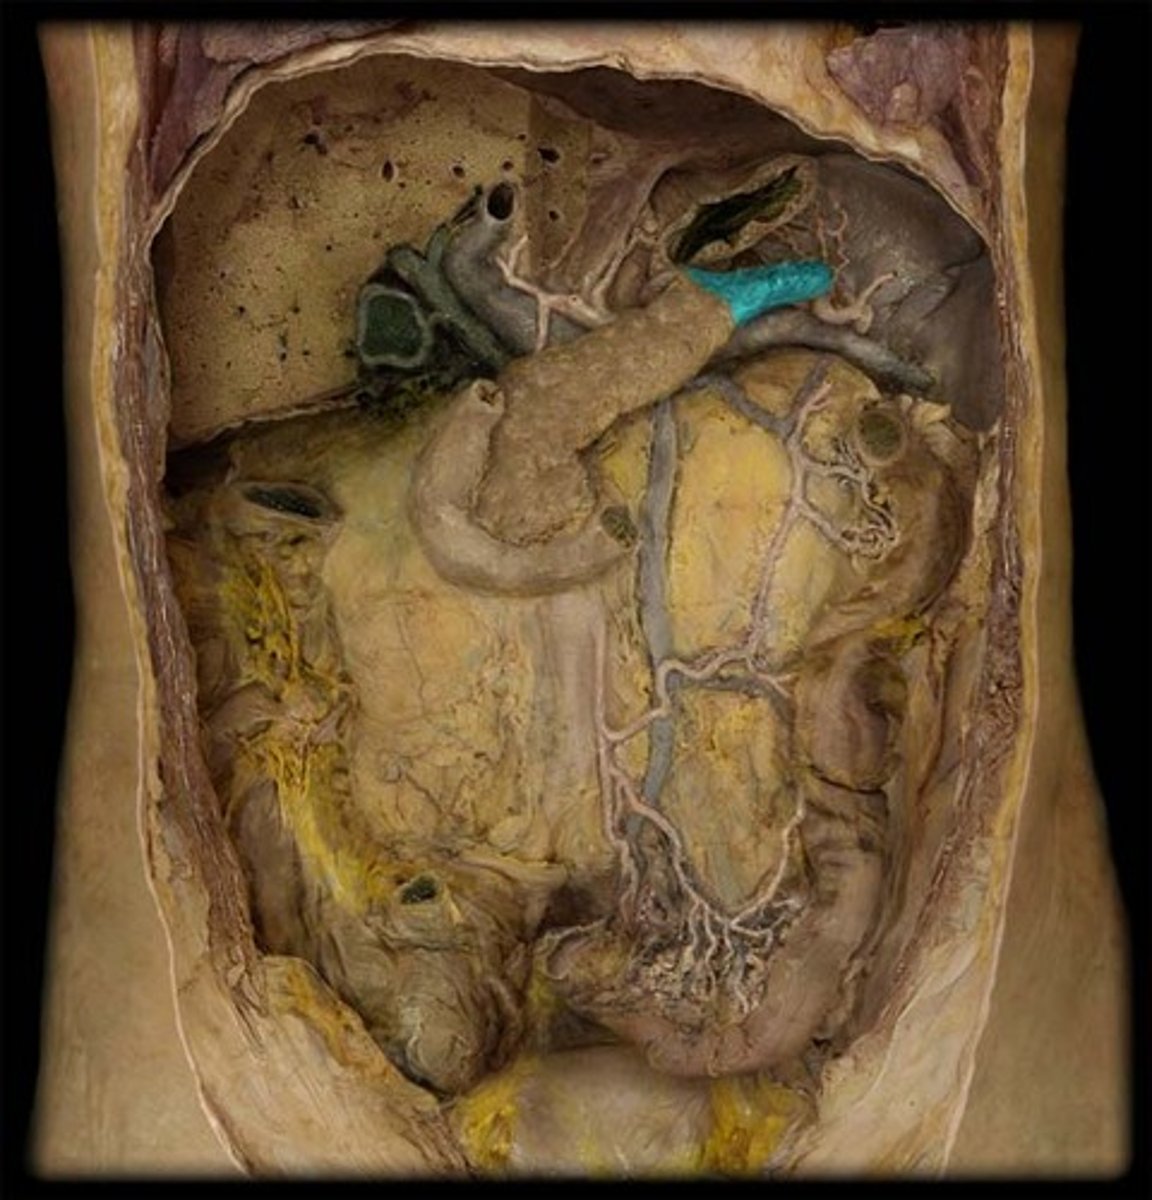

Porta hepatis structure consists of...

Proper hepatic artery

Hepatic portal vein

Common bile duct

What are these?

Hepatic duct (right and left)

What is this?

Common hepatic duct

Cystic duct

Head of the pancreas

Body of the pancreas

Tail of the pancreas

Pancreatic duct